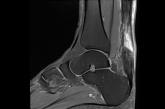

Nonoperative management for acute Achilles tendon rupture results in patient-reported outcomes similar to surgery at 1 year—but higher rates of...